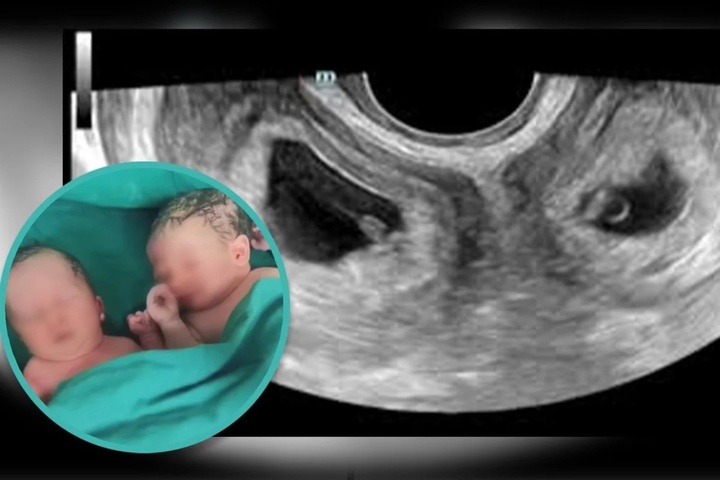

Người phụ nữ họ Li có hai tử cung vừa sinh con. (Ảnh: SCMP)

Khi hai thai nhi hơn 8 tháng, Li được các bác sĩ chỉ định sinh mổ. Các bé chào đời khỏe mạnh tại Bệnh viện số 4 Tây An, tỉnh Thiểm Tây. Bé trai nặng 3,3kg và bé gái nặng 2,4kg. Li cùng hai con được xuất viện sau khi sinh 4 ngày.

Tình trạng tử cung đôi rất hiếm gặp nhưng việc phụ nữ sinh con thành công ở hai tử cung thậm chí còn hiếm gặp hơn. (Ảnh: Douyin)